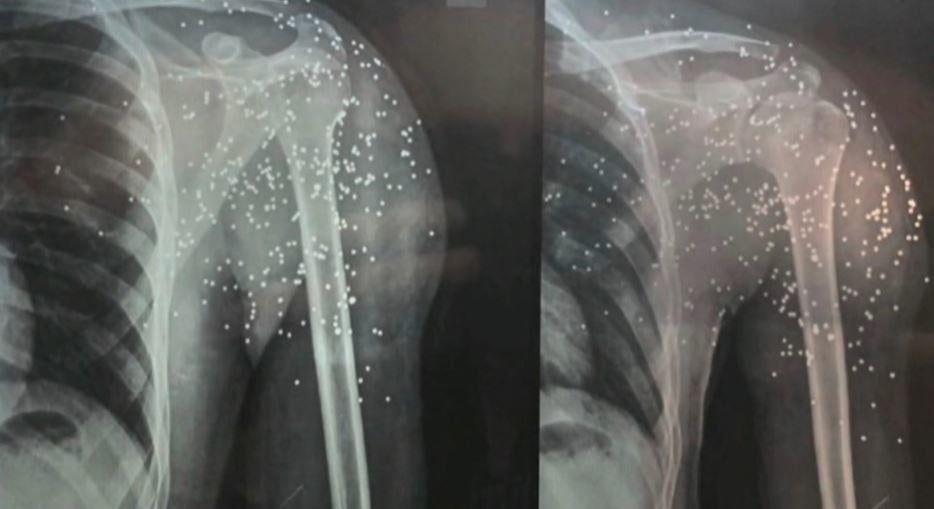

"Three shots hit my right hand and one shot hit my left eye," she said, adding her father had also been shot in the hand.

Amnesty International and other rights groups have accused Iranian security forces of partially or completely blinding multiple protesters, firing live ammunition and metal pellets at close range.